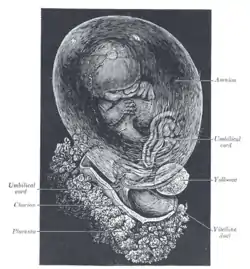

Human placenta immediately post birth. Fetus of about 8 weeks, enclosed in the amnion. Magnified a little over two diameters.

Fetus of about 8 weeks, enclosed in the amnion. Magnified a little over two diameters. Placenta with attached fetal membranes, ruptured at the margin at the left in the image